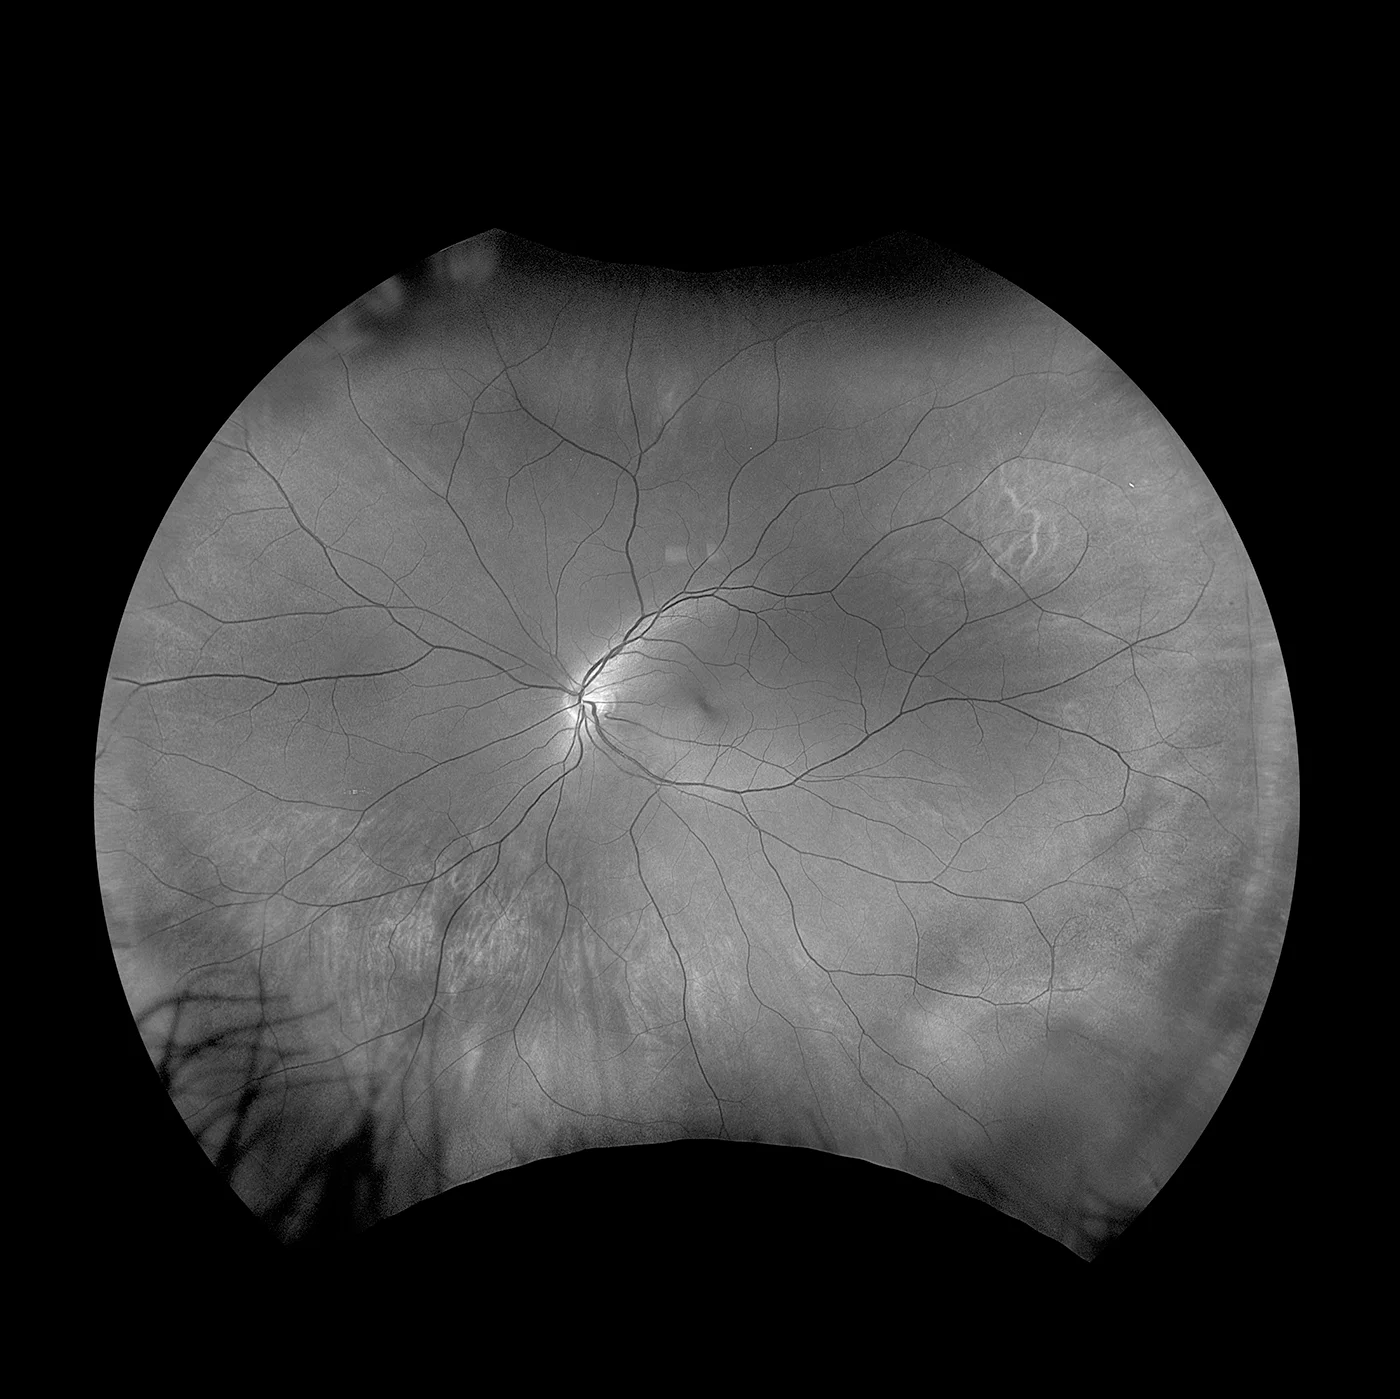

optomap Sensorische Netzhaut

Im Gegensatz zu konventionellen Geräten, die mit weißem Licht arbeiten, scannen bei dieser Technologie zwei Laser-Wellenlängen mit niedriger Leistung gleichzeitig die Netzhaut. So können die retinalen Substrukturen in ihren jeweiligen Laserseparationen betrachtet werden. Die rotfreie Sicht scannt von der sensorischen Netzhaut bis zu den Pigmentepithelschichten.